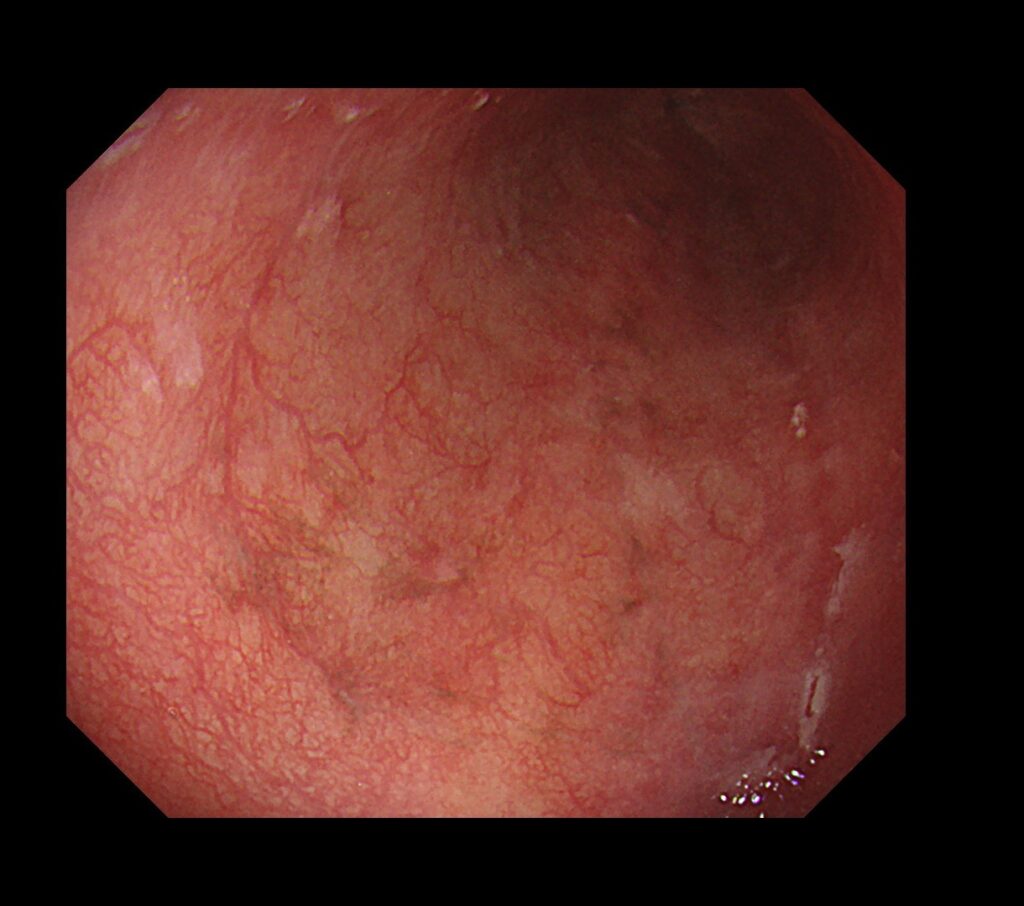

通常観察では周囲粘膜より、やや茶食の領域が散見されています。

この時点で、入念に食道癌の発見に集中します。

近傍に癌を疑う所見を認め、拡大観察可能な内視鏡に切り替え、再度観察。